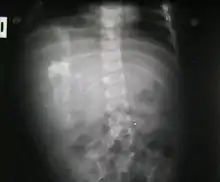

Fetus in fetu may be a parasitic twin fetus growing within its host twin. Very early in a monozygotic twin pregnancy, in which both fetuses share a common placenta, one fetus wraps around and envelops the other. The enveloped twin becomes a parasite, in that its survival depends on the survival of the host twin, by drawing on the host twin's blood supply. The parasitic twin is anencephalic (without a brain) and lacks some internal organs, and as such is unable to survive on its own. As the host twin has to "feed" the enveloped twin from the nutrients received over a single umbilical cord, they usually die before birth.